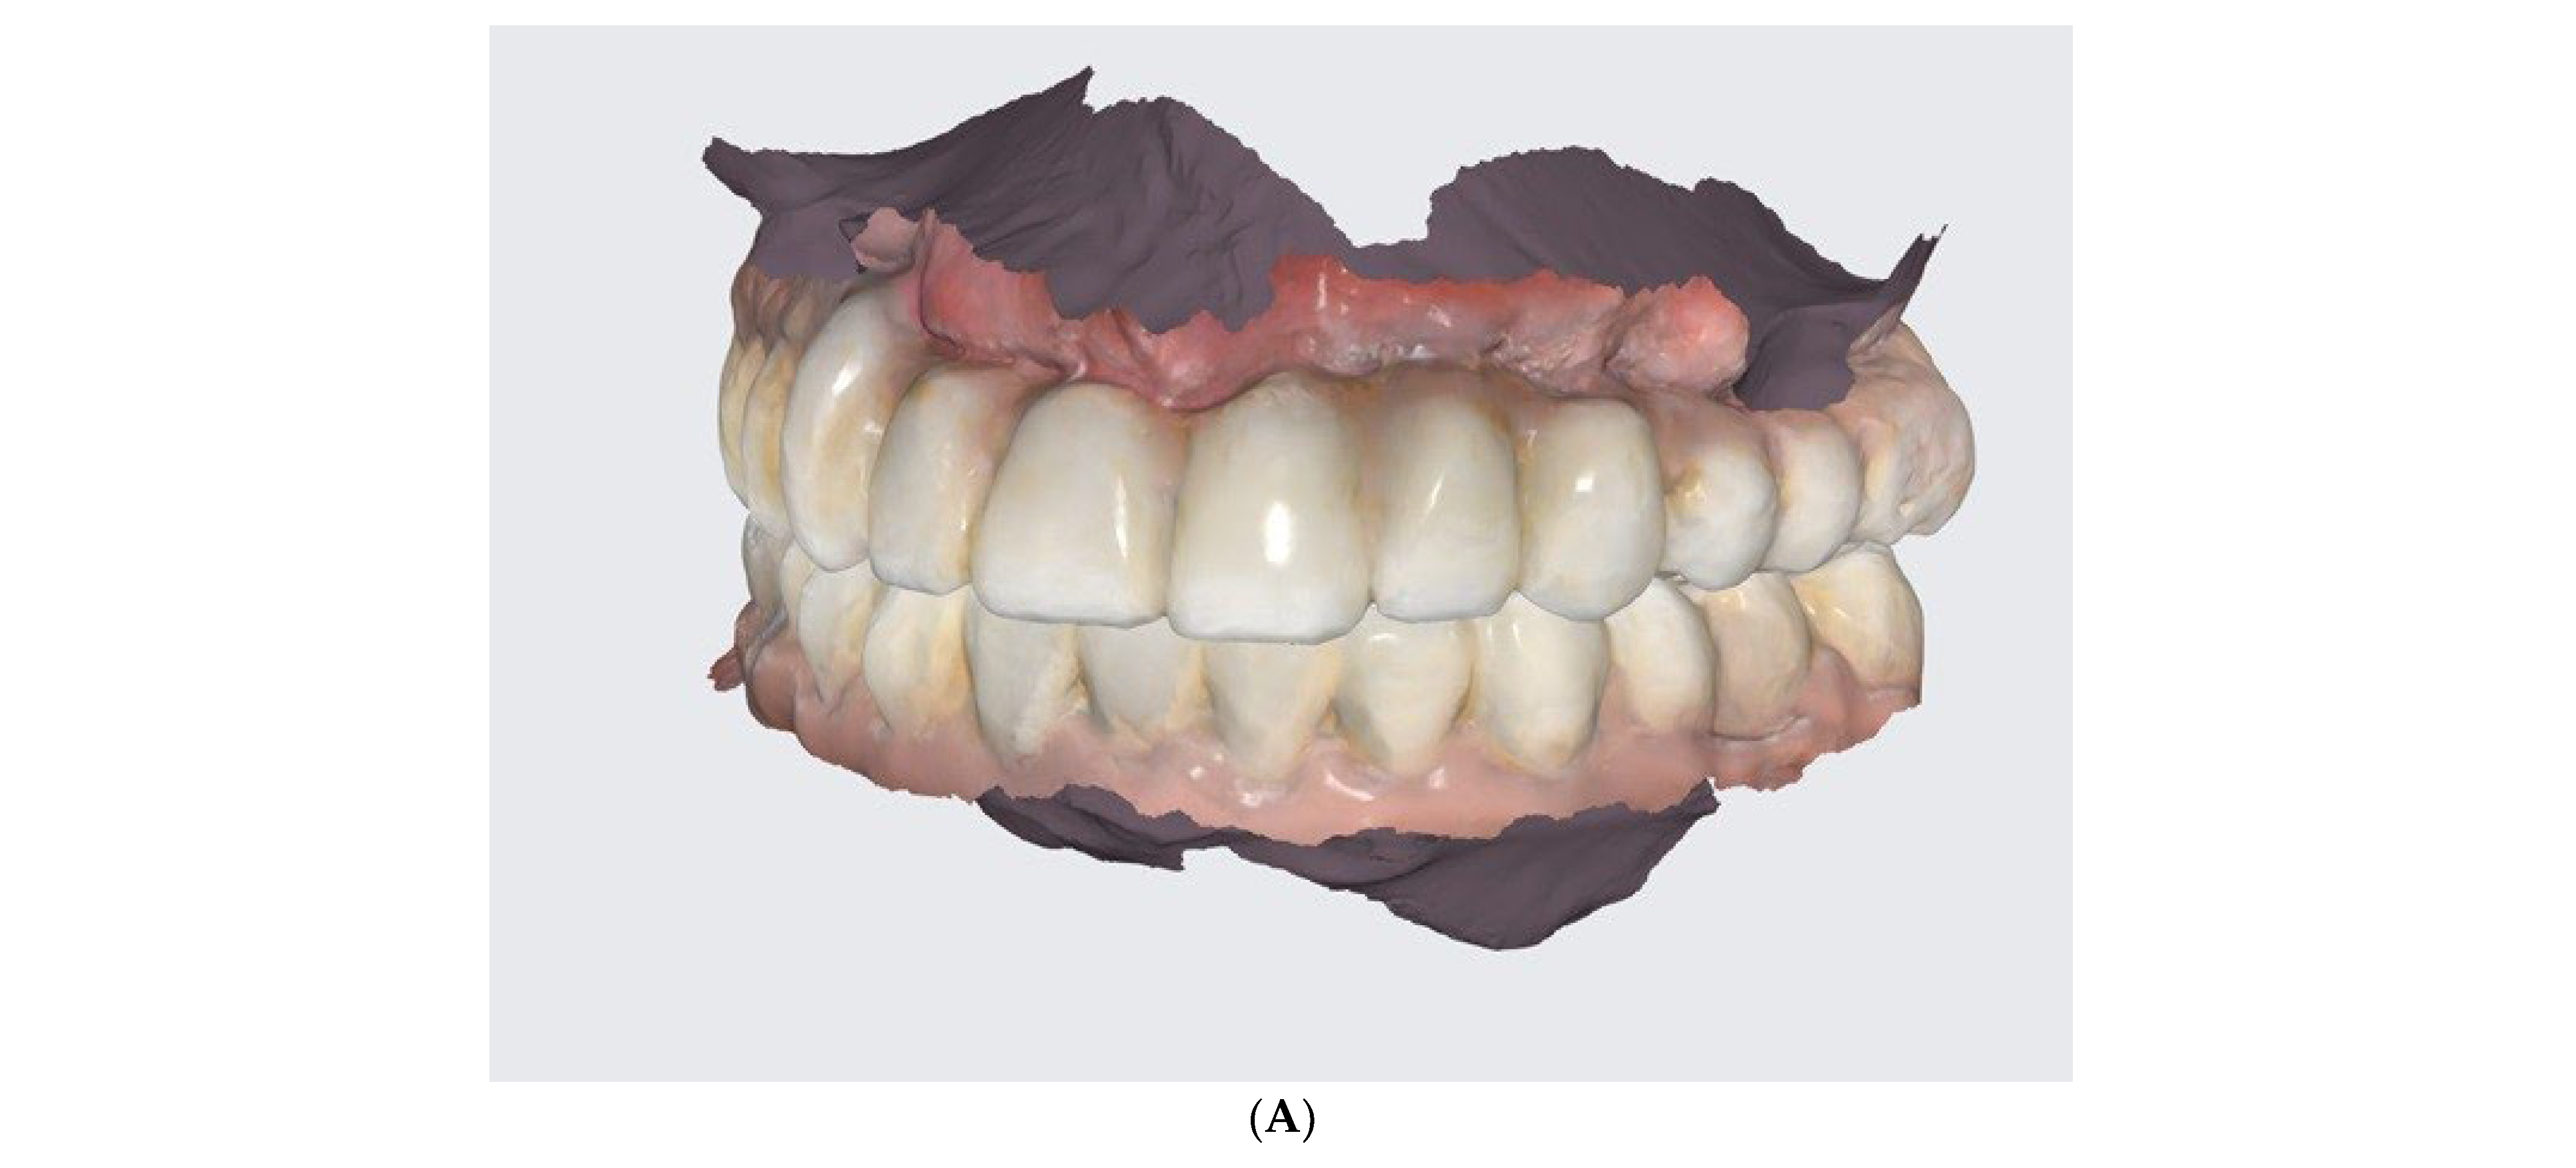

- Conduction of DSD, an I.O. scan, a 360° scan of removals, and CBCT after the healing phrase.

- The conduction of an analogue impression, an I.O. scan, a removable 360° scan, and a scanflag scan.